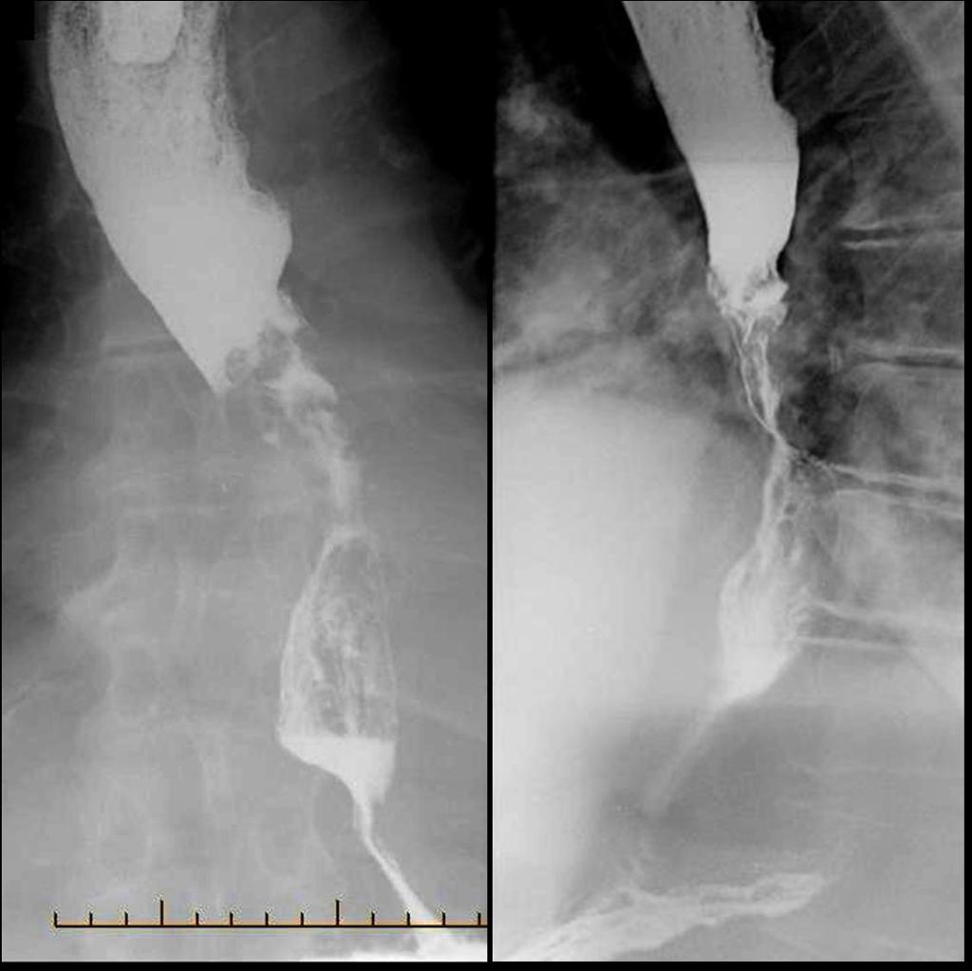

Apple core lesion - oesophageal carcinoma

Achalasia

Autosomal Dominant Polycystic Kidney Disease